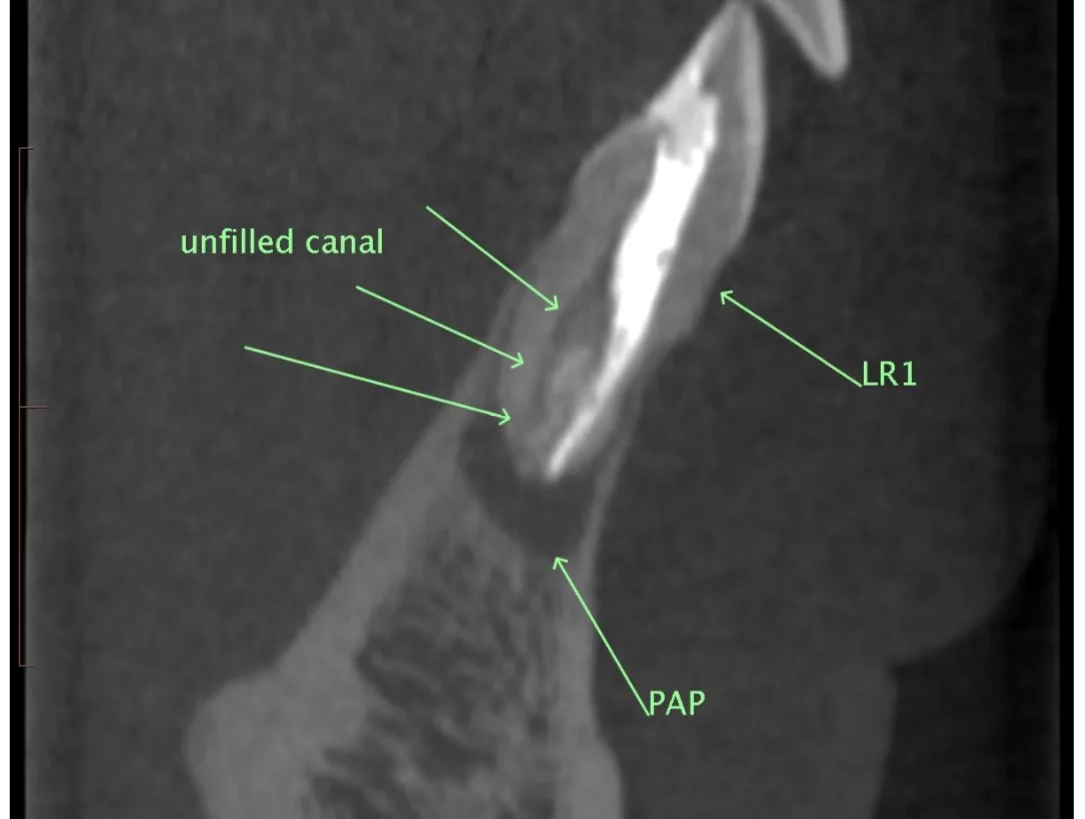

Open demo endo report